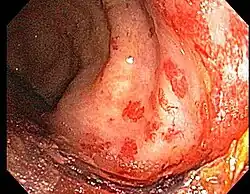

Chronic radiation proctitis

- Chronic Radiation Proctitis

-

-

-

- Etiology: obliterative endarteritis and chronic mucosal ischemia, leading to progressive epithelial atrophy and fibrosis. Ultimately, development of a chronically ischemic intestine prone to fibrosis and bleeding

- Diagnosis: colonoscopy, barium studies if suspecting strictures and fistulas